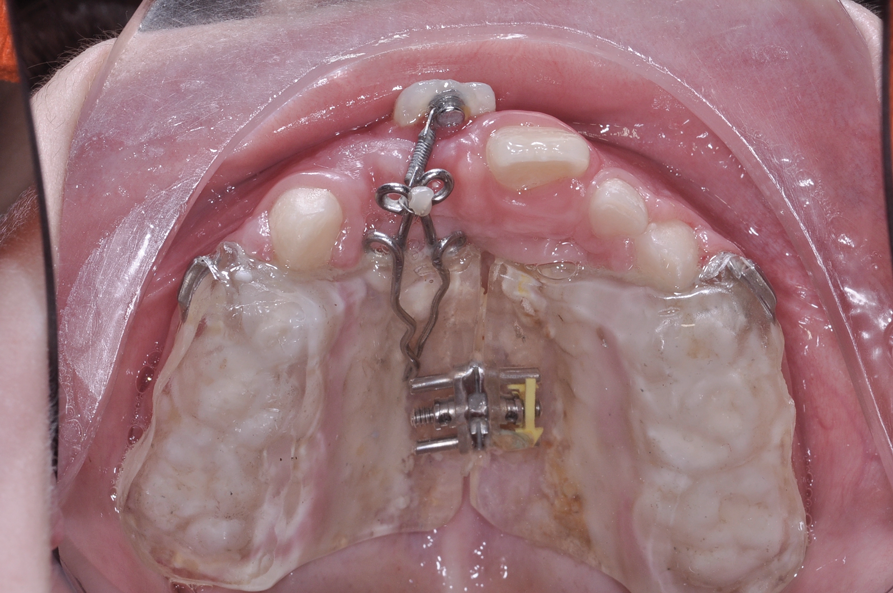

Fig 12. After expansion of the maxillary arch, the modified palatal expander was used for traction of the impacted maxillary right central incisor. Fig 12: Palatal expansion to gain space in the premaxilla for the impacted maxillary right central incisor. Fig 13: Traction of the impacted maxillary right central incisor through a palatal orthodontic attachment and the use of a power arm incorporated in the expander. Fig 14: Detailing the position of the impacted maxillary right central incisor with orthodontic fixed appliances.

Figure 12

Fig 13. After expansion of the maxillary arch, the modified palatal expander was used for traction of the impacted maxillary right central incisor. Fig 12: Palatal expansion to gain space in the premaxilla for the impacted maxillary right central incisor. Fig 13: Traction of the impacted maxillary right central incisor through a palatal orthodontic attachment and the use of a power arm incorporated in the expander. Fig 14: Detailing the position of the impacted maxillary right central incisor with orthodontic fixed appliances.

Figure 13

In reviewing this case more closely, the sequence usually starts with a space opening (Figure 12 through Figure 14). Palatal expansion is generally performed even without the presence of a posterior dental crossbite, as many patients with impacted maxillary central incisors are deficient in the development of the anterior portion of the maxilla.7,11 The use of sliding mechanics with open coils in conjunction with simple fixed systems is preferred to removable appliances since they deliver a light, continued force instead of an intermittent force.7 Interarch mechanics allow space to be gained for either the natural eruption or the surgical/orthodontic traction of the impacted maxillary central incisor.7 After palatal expansion, rigid structures, such as fixed transpalatal arches soldered to upper first molar bands, might first be used to anchor the active traction of the impacted tooth. Later, orthodontic fixed appliances reportedly have been used in the maxillary anterior to detail the position of the maxillary central incisor in the arch.11 Frequently, power arms are incorporated into palatal expanders.12 Fixed systems initially employ flexible nitinol wires and round stainless-steel wires. After initial leveling, rectangular stainless-steel wires have been used as part of several protocols to produce torque and place the roots of the resolved impacted central incisor in the proper position in its apical base.3,7,13 Orthodontic traction is conducted with different systems based on the preference of the clinician.3,7,10